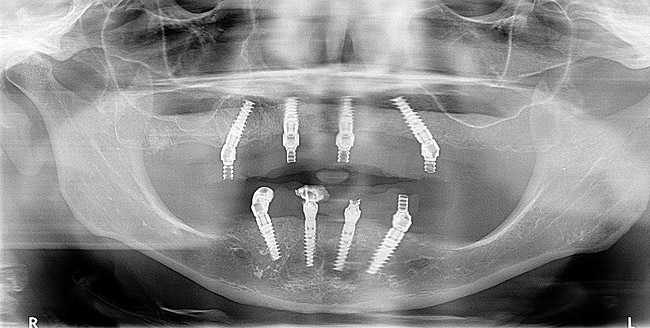

Figure 7  A postoperative panoramic radiograph showing implant placement.

Figure 7

Vertical dimension of occlusion was recorded before anesthetizing the patient with IV sedation containing 75 mg of Demerol, 12.5 mg of Versed, 2% Xylocaine 1:100,000 epinephrine, and 0.5% Marcaine 1:200,000 epinephrine. Extraction of teeth Nos. 3, 5, 6, and 7 from the maxillary was performed first, followed by maxillary alveoplasty. Next, a hole was created from the anterior wall of the floor of the left and right sinus. Implant placement was performed with the aid of a surgical template (All-on-4). A 2-mm drill site was created midline and an implant stent was placed. Next, a posterior implant, at no more than a 45° angulation, was placed 4 mm in front of the sinus. The head of the implant in the second bicuspid area was emerged (4.3 mm x 15 mm). The drill sites were left underprepared, especially in the maxilla. A 30° multiunit angled abutment was placed. Two straight anterior implants were placed into the nasal floor (4.3 mm x 13 mm) and the maxillary anterior implant was placed at a 17° angle. The angled implants would accommodate for the lack of healthy bone structure by increasing bone-to-implant contact.

Mandibular teeth Nos. 22 through 27 were extracted and a radical mandibular alveoplasty was performed leaving approximately one quarter of the extraction sockets remaining. Having located the right and left mental foramen nerve, a 2-mm drill site was created midline and the implant stent was placed. Two 30° angled implants were placed in the mandibular second bicuspid area—right 4.3 mm x 18 mm and left 4.3 mm x 18 mm at no more than a 45° angulation. Next, straight implants were placed, right 4.3 mm x 13 mm and left 3.5 mm x 13 mm. Finally, the anterior implants were placed at a 17° angulation. Multi-unit abutment healing caps were placed onto the abutments.

The patient was allowed to heal, and postoperative follow-up treatments were performed until osseointegration was complete (Figure 5 and Figure 6). Three months later, the provisionals were removed and abutment-level impressions were taken for the definitive restoration. Pickup impressions of the provisional prosthesis served as verification jigs and were mounted. While the patient waited for the return of their temporary restorations, tooth selection and shape were discussed, agreeing upon a polymethyl methacrylate acrylic material (PMMA), known for providing long-lasting restorations. While earlier generations of denture teeth were likely to fracture, Mondial® Denture Teeth (Kulzer, www.heraeus-dental-us.com) were chosen in this particular case due to their voidless, high-density center specifically designed to accommodate the opening for the insertion of the screw without weakening, for screw-retained prostheses. Alternatives include: Phonares® (Ivoclar Vivadent, www.ivoclarvivadent.com), Portrait IPN (Dentsply Sirona, www.dentsplysirona.com), and others.